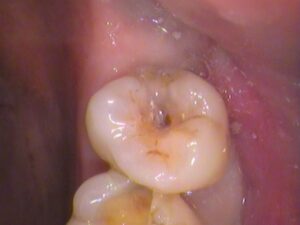

虫歯をしっかりと取ったところです。

虫歯の取り残しの無いように染色されないところまで、きれいに取ります。